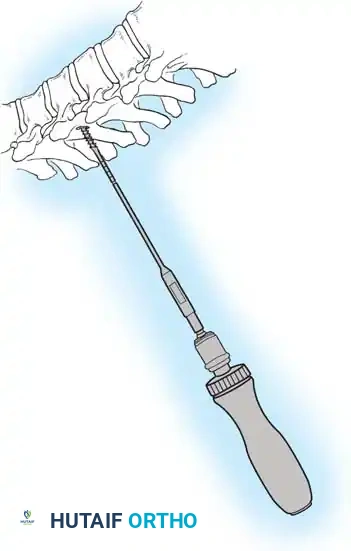

Deep Subperiosteal Dissection

- Cartilaginous Cap Incision: Incise the cartilaginous cap overlying the spinous processes precisely in the midline. Note that in severe scoliosis, the midline may be significantly deviated due to apical vertebral rotation.

- Cobb Elevation: Utilizing a Cobb elevator combined with electrocautery, expose the spinous processes subperiosteally. Move the cartilaginous caps and attached paraspinal muscles laterally.

- Direction of Dissection: It is anatomically advantageous to dissect from caudad to cephalad. The short rotator muscles (multifidus and rotatores) and ligaments of the spine attach obliquely, pointing superomedially. Sweeping upward works with the grain of these fibers, allowing for a cleaner, faster subperiosteal release.

- Maintaining Tension: As the exposure deepens, sequentially advance the Weitlaner or Cerebellar retractors. Constant, firm retraction is the surgeon's best tool for passive hemostasis.

Lateral Exposure and Hemostasis

- Transverse Process Exposure: Extend the subperiosteal dissection laterally, first exposing the facet joints, and then continuing out to the tips of the transverse processes bilaterally.

- Segmental Vessels: As you dissect lateral to the facet joints, you will encounter the posterior branches of the segmental vessels. These must be meticulously identified and coagulated with bipolar or monopolar cautery to prevent insidious bleeding.

- Facet Cleaning: Use a sharp curet and a pituitary rongeur to completely excise the facet capsules and clean the interspinous ligaments.

Clinical Pearl: Always direct your curet from the midline laterally when cleaning the facet joints. This directional force ensures that if the instrument slips, it moves safely away from the spinal canal, preventing catastrophic dural tears or iatrogenic spinal cord injury.

Fig. 38-25: Cobb curets utilized to meticulously clean the facets of all ligamentous and capsular attachments.